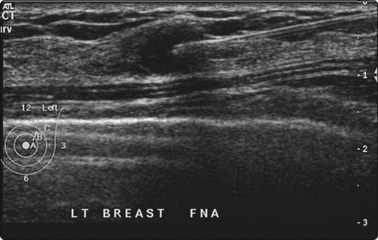

Many operators prefer US guidance for its speed, flexibility and real-time facilities. The patient is also able to lie comfortably during the procedure. The method is limited by the type of lesion; many microcalcifications are not visible on ultrasound examination. There is also the slight risk of pleural puncture or pneumothorax if used by inexperienced operators. The needle should run parallel to the chest wall and never be introduced perpendicular to the ribcage (see Fig. 3.4). By positioning the patient and compressing the breast, the depth of the lesion can be reduced. Breast lesions often require multiple sampling, typically best achieved using ultrasound guidance (Fig. 3.5).

image

Fig. 3.5 FNA biopsy of a breast lesion with aggressive features

Several passes may be necessary to yield sufficient cells.